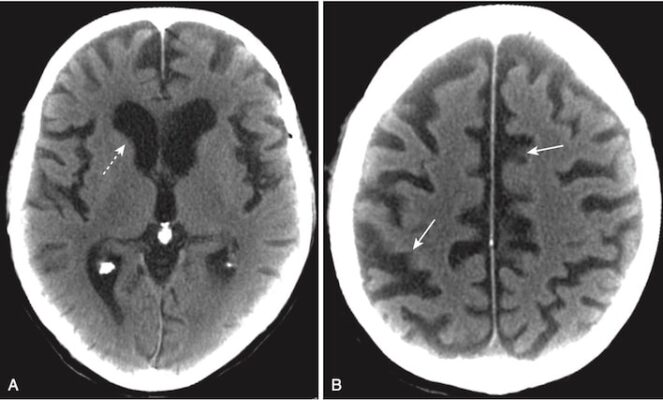

- Trong não úng thủy, các não thất thường bị giãn rộng một cách không cân đối so với với rãnh não, trong khi trong teo não thì cả não thất và rãnh não đều giãn rộng.

- Sừng thái dương đặc biệt nhạy với tăng áp lực dịch não tủy. Trong trường hợp không có não úng thủy, sừng thái dương hầu như không nhìn thấy được. Với não úng thủy, sừng thái dương có thể có kích thước lớn hơn 2 mm (Hình 22).

- Não úng thủy thông (communicating hydrocephalus) là do các bất thường ức chế tái hấp thu dịch não tủy, thường xảy ra ở nhung mao màng nhện (Hình 23).

- Bình thường dòng chảy dịch não tủy qua các não thất và nền sọ không bị cản trở. Sự tái hấp thu qua nhung mao có thể bị hạn chế bởi những nguyên nhân như xuất huyết dưới nhện hoặc viêm

- màng não.

- Điển hình, não thất 4 bị giãn ra trong não úng thủy thông và có kích thước bình thường trong não úng thủy thông.

- Não úng thủy không thông xảy ra do các khối u, nang hoặc các tổn thương gây tắc nghẽn khác không cho dịch não tủy thoát ra khỏi các não thất (Hình 24).

- Các dấu hiệu về hình ảnh học cũng tương tự như các dạng não úng thủy thông khác và gồm giãn não thất, đặc biệt là sừng thái dương, với các rãnh não bình thường hoặc dẹt (Hình 25).